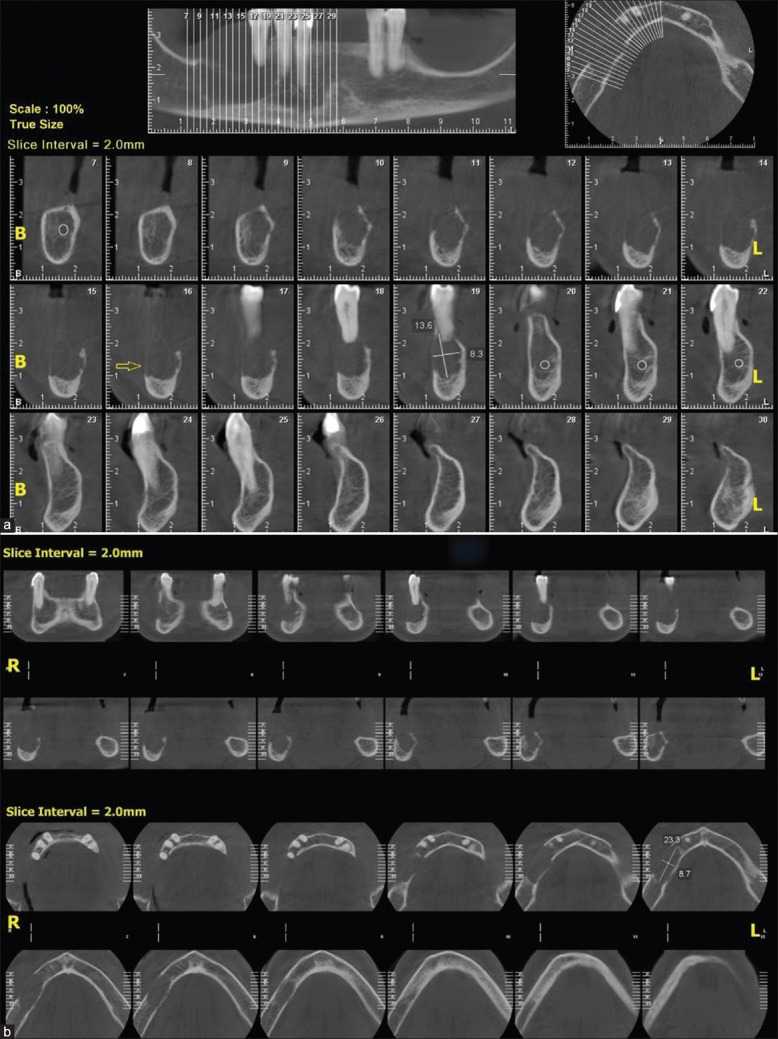

恶性肿瘤能够在远离原发部位的地方生长。乳腺癌、前列腺癌、肾癌、甲状腺癌和肺癌通常转移到骨。下颌转移是罕见的,但可能发生比一般估计更频繁。甲状腺滤泡癌是滤泡细胞分化的肿瘤,由微滤泡结构组成,滤泡由立方上皮细胞排列。这种类型的癌症在术前或术中治疗阶段很难诊断。在这里,我们报告一个病例滤泡癌的甲状腺谁是转诊由于下颌骨病变。

Malignant tumors are able to grow at sites distant from the primary site of origin. Breast, prostate, renal, thyroid, and lung carcinomas commonly metastasize to bone. Jaw metastasis is rare but may occur more often than generally estimated. Follicular carcinomas of the thyroid gland are tumors of follicular cell differentiation that consist of a microfollicular architecture with follicles lined by cuboidal epithelial cells. It is very difficult to diagnose this type of cancer at the preoperative or intraoperative stage of treatment. Here, we report a case of follicular carcinoma of the thyroid gland who was referred due to a mandibular lesion.